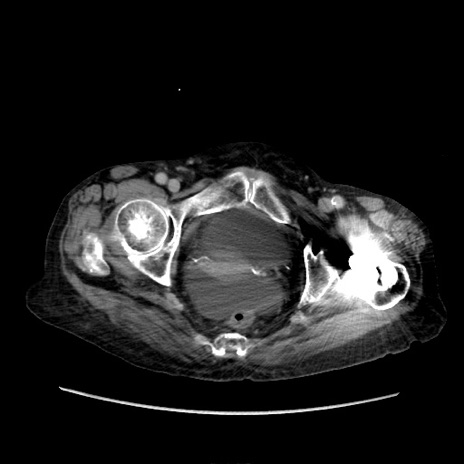

症例31(横断像)

【症例】80歳代 女性

【主訴】腹部膨満感

【現病歴】他院にて肝硬変にてフォロー中。1週間前から便秘、腹部膨満感、臍部腫瘤あり受診となる。

【既往歴】肝硬変

【身体所見】腹部膨隆あり、皮膚変化なし、疼痛なし。

【データ】WBC 4600、CRP 0.25